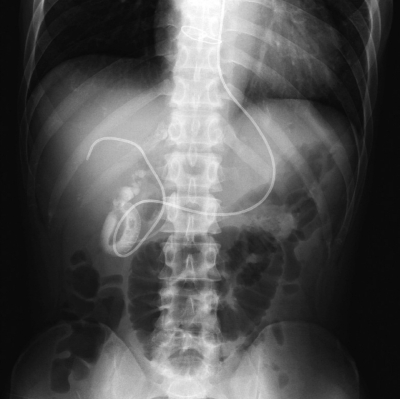

ある患者に対して処置を行った後の腹部エックス線写真を示す。

内視鏡的経鼻胆管ドレナージ(Endoscopic nasobiliary drainage : ENBD)である。